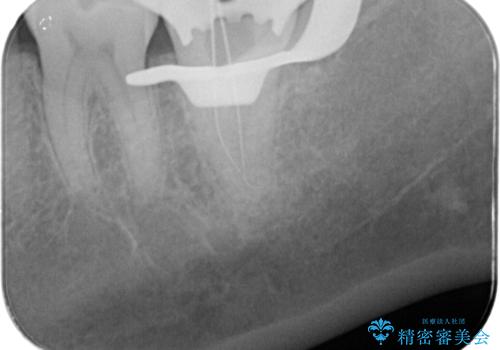

樋状根(といじょうこん)の根管治療

- 昨夜から、寝れないぐらいズキズキ痛む歯があることを主訴に来院されました。

歯髄診にて患歯を特定し、不可逆性歯髄炎の診断のもと治療を行っています。

治療中には過去に修復された材料の下に虫歯を認めましたが、破折線はみとめられませんでした。

治療後すぐに症状は改善され、今後クラウン修復を行う予定です。